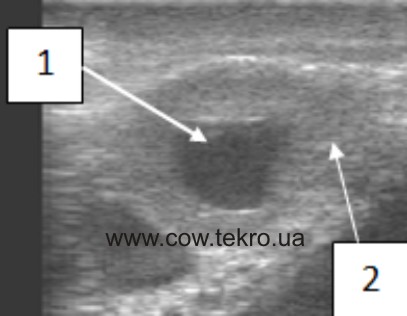

За ультразвукового дослідження гонад корів мають однорідну ехоструктуру, нормальні розміри, кількість везикульрних фолікулів зменшена, а жовті тіла відсутні (рис. 2).

Рисунок 2 –Ехограма яєчника корови за гіпофункції: 1 – тканинии яєчника